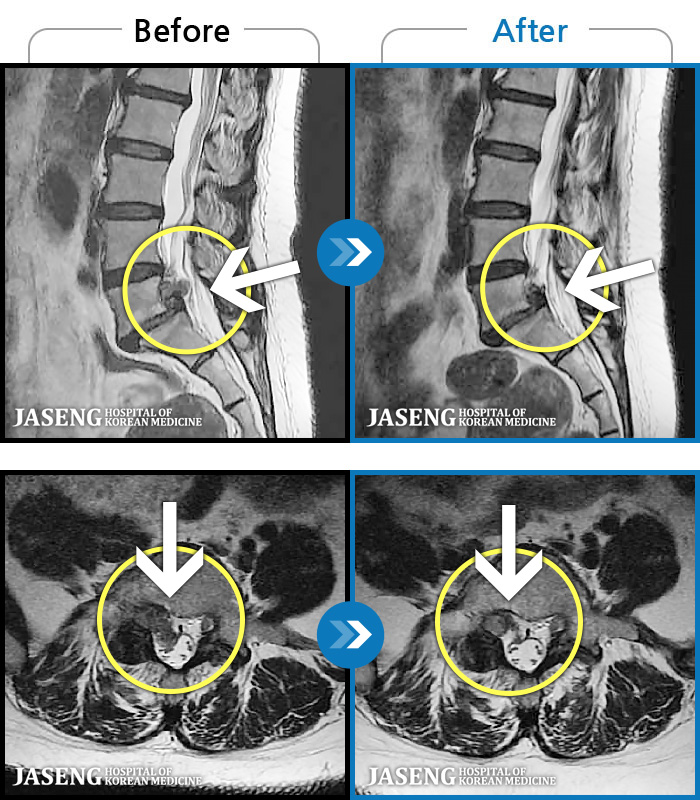

123 MRI ũ ʸ Ȯϼ.

ó ̾ ߰, ణ ٷϵ ݵǾ ϻȰ ¿ϴ. |

[õ] 24.04.06~24.11.16